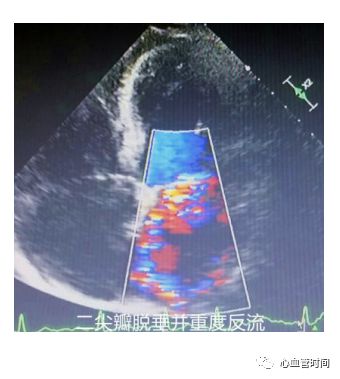

脱垂时可见

蓝色花彩血流于收缩期出现,且往往是大量

偏心性反流

。

同时对于心梗特别是

下壁心梗

,出现偏心性反流要考虑有无

乳头肌功能不全;

脱垂时可见

蓝色花彩血流于收缩期出现,且往往是大量

偏心性反流

。

同时对于心梗特别是

下壁心梗

,出现偏心性反流要考虑有无

乳头肌功能不全;

瓣膜反流往往不是一个切面就可以定量的,反流是一个立体的存在,千万

不要被单一画面蒙蔽了双眼

,有时一个切面只能看见一「细条」,而另一切面就是一「大片」,一定要

结合各个切面各个角度

综合评价。